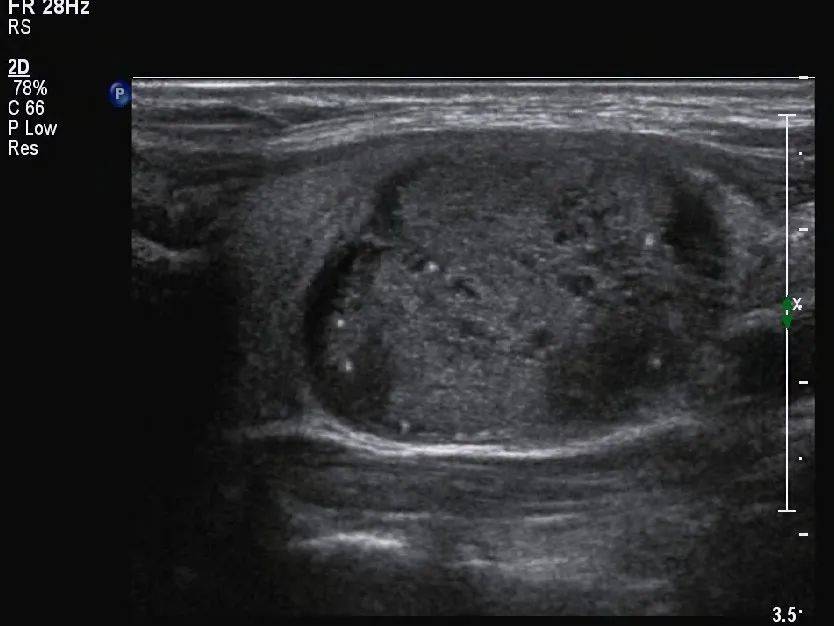

甲状腺形态失常,左侧叶增大,内部回声不均匀,见囊实混合性结节,大小约 33mm×19mm×28mm ,形态规则,边界清,纵横比 <1 ,内部以实性为主,实性部分见少许散在点状强回声(图 1 、图 2 ),结节周边伴低回声声晕,声晕厚度不均匀(图 3 ), CDFI:结节周边见环绕血流信号,内部见不规则分布的血流信号,局部较丰富(图 4 、图 5 )。SMI:结节局部微细血流信号丰富(图 6 )。

图 1 囊实性结节,以实性为主,内见多个散在分布的点状强回声